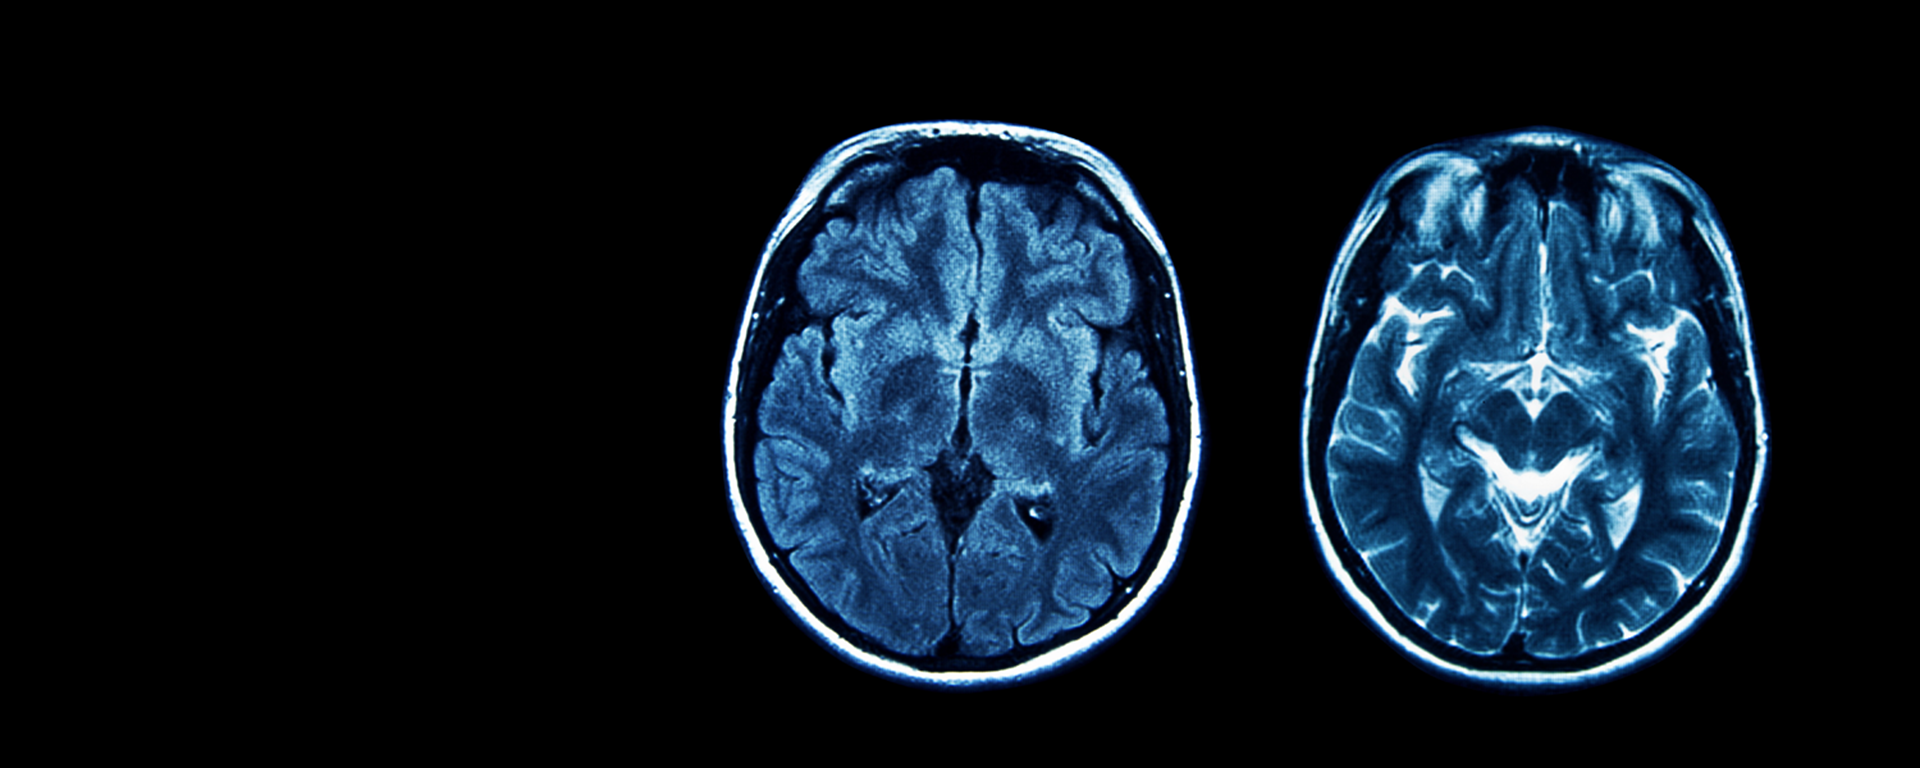

A concussion is a type of brain injury, most often caused by a hit to the head, neck, face, or body. They cause changes in how the brain works but these changes can’t always be seen on a CT scan or MRI. A concussion can change the way you think and feel. Symptoms can vary and present differently depending on the person and injury.